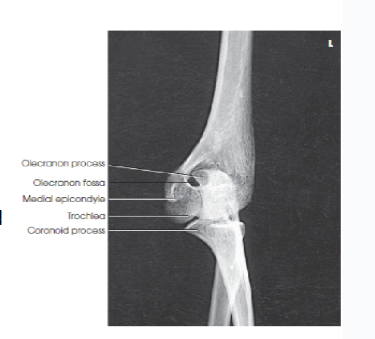

Eval/structures: what happens to the olecranon process in an AP oblique elbow medial rotation?

the olecranon process appears within the olecranon fossa